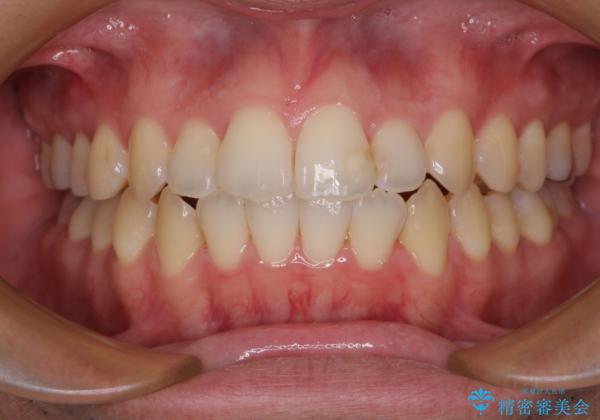

開咬とデコボコを整える インビザライン矯正治療

- 前歯の開咬と叢生を気にして来院された患者様です。

開咬の治療は、前歯を閉じるように動かすとともに、上下臼歯を圧下(骨内にめり込ませる)させることで進めて行きます。

インビザラインは臼歯の圧下を効果的に行えるため、インビザラインを用いて矯正治療を行うこととしました。また、アンカースクリューを用いて、口元の突出感の改善を図りました。